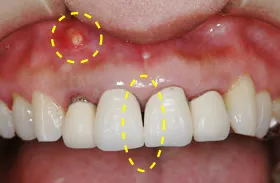

審美的観点から差し歯をインプラントにした治療例

他院にて歯茎がくぼみ差し歯が歯茎から浮いてしまい見栄えが悪い為、ブリッジを勧められました。

健康な両サイドの歯を削らないといけない為インプラントを希望されましたが、上顎の骨の量が足りずインプラントが出来ないとの事で他院から紹介された患者様です。

差し歯を除去した写真です。

歯茎を切開すると、上顎に大きな空洞がありインプラントを埋め込む為の骨がありません。

造骨材で骨を作っている写真です。

骨を造った後、インプラント治療を行いました。

審美的にも回復し、満足して頂きました。

| 主訴 | 歯茎のくぼみが気になる、他の歯は削りたくないのでインプラントにしたい |

|---|---|

| 治療方法 | GBR治療+インプラント治療 |

| 治療期間 | 約1年 |

| 通院回数等 | 12回位 |

| 費用 | 約65万円 |

| リスク・副作用 | 術後の腫れ・痛み |